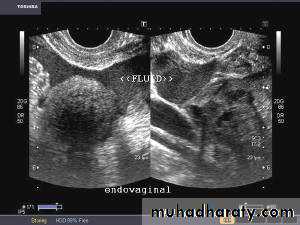

Hemorrhagic cyst of ovary with ruptured ectopic pregnancy:

This female patient has a left ovarian hemorrhagic cyst (see ultrasound image above-left). In addition, there is a large collection of free fluid with particulate matter in the pelvis. The right fallopian tube is thickened with a ring shaped mass. This suggests that there is significant hemorrhage into the pelvis due to a ruptured ectopic pregnancy (right tubal ectopic gestation). The left ovarian hemorrhagic cyst appears intact, ruling out ruptured hemorrhagic cyst.